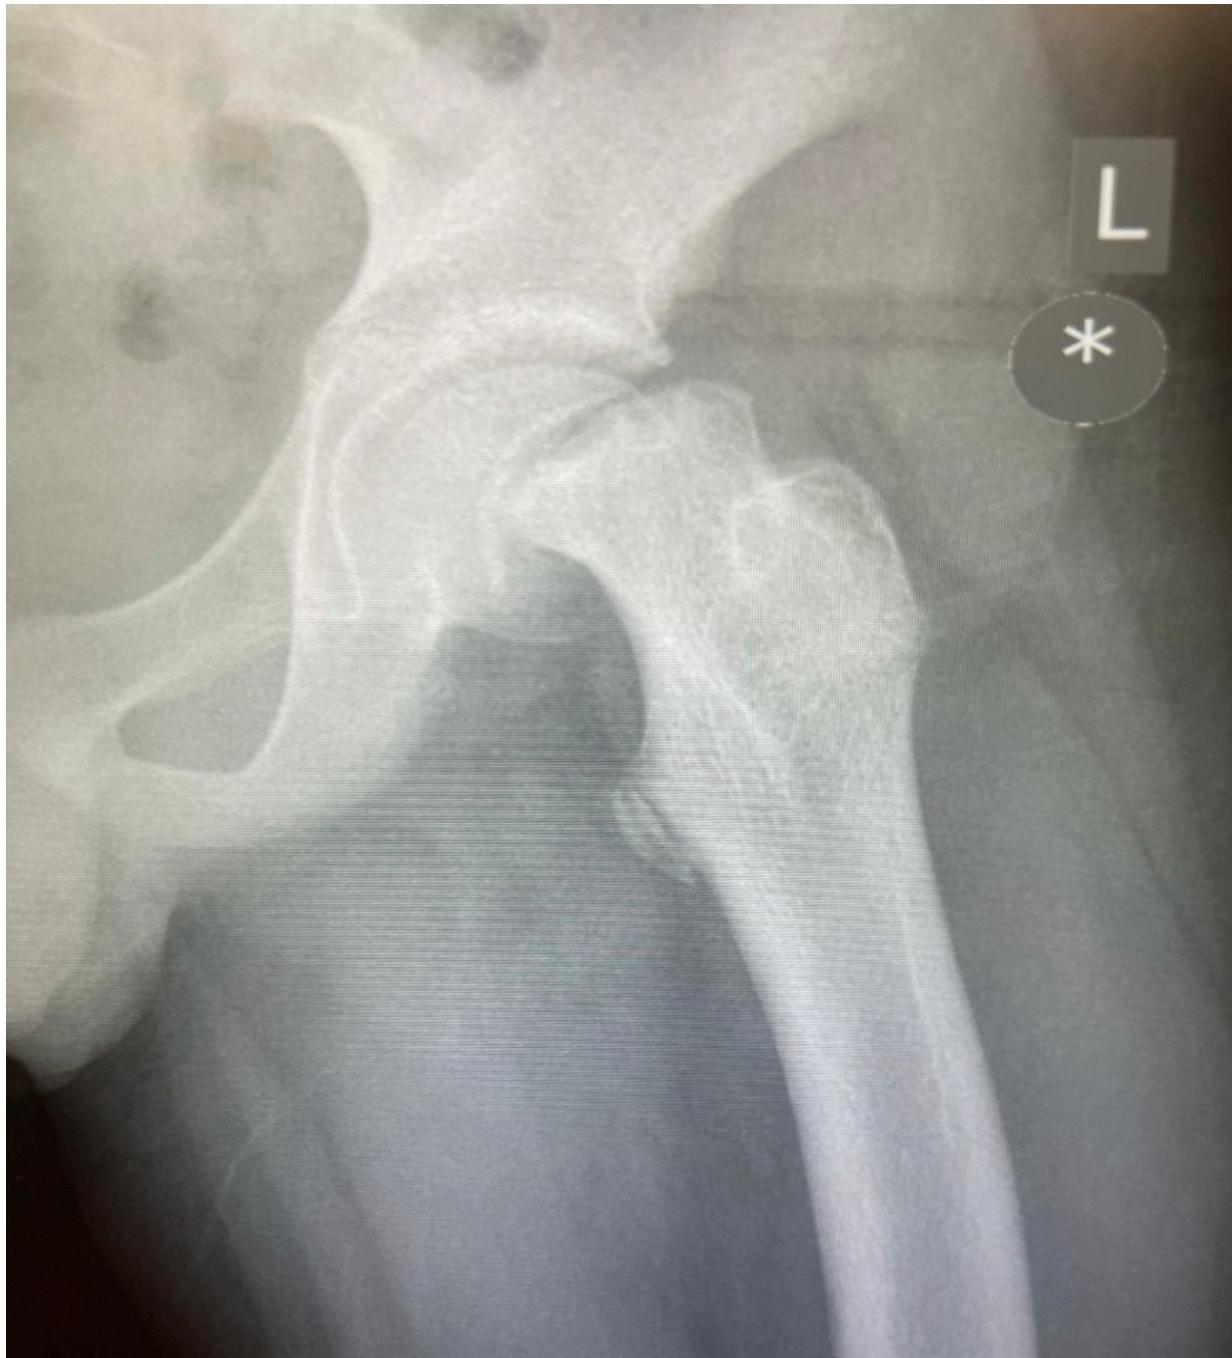

X-ray shows: Posteroinferior displacement of the left capital femoral epiphysis

Diagnosis

Slipped capital femoral epiphysis (SCFE) at left hip joint